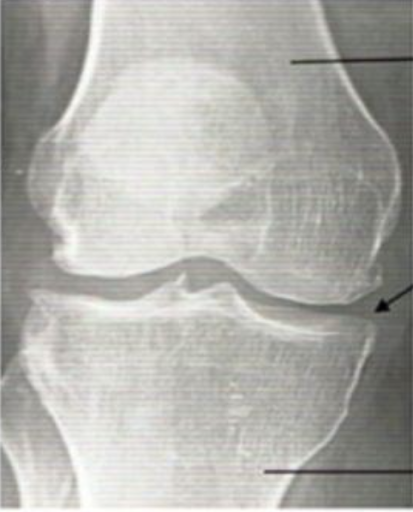

Would you like your knees to go from this:

According to a recent study, there is a compound that can help do that... it's shockingly affordable (and delicious).